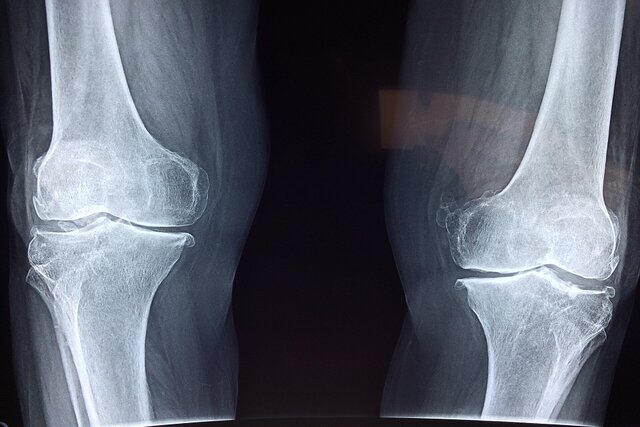

به گزارش نبض وطن، در مجموع ۱۴۵۴ تصویر اشعه ایکس با استفاده از سیستم دانشمندان مورد تجزیه و تحلیل قرار گرفت. میزان حساسیت عملکرد برای کمر و استخوان ران بیماران مبتلا به کاهش تراکم استخوان به ترتیب ۸۶.۴ و ۸۴.۱ درصد بود.

به نقل از مدیکالاکسپرس، میزان اختصاصی بودن آن نیز ۸۰.۴ و ۷۶.۳ درصد بود. حساسیت، توانایی آزمایش در شناسایی صحیح افراد مبتلا به پوکی را نشان میداد در حالی که اختصاصی بودن، توانایی آن را در شناسایی صحیح افراد بدون پوکی استخوان نشان میداد. این آزمایش همچنین از حساسیت و اختصاصی بودن بالایی برای دستهبندی بیماران مبتلا به پوکی استخوان و بدون آن برخوردار بود.

دکتر تورو مورو، نویسنده مسئول این مقاله از دانشگاه توکیو، میگوید: اندازهگیری تراکم مواد معدنی استخوان برای غربالگری و تشخیص پوکی استخوان ضروری است، اما دسترسی محدود به تجهیزات تشخیصی به این معنی است که میلیونها نفر در سراسر جهان ممکن است از این بیماری بیاطلاع بمانند.

این سیستم هوش مصنوعی پتانسیل تبدیل عکسهای رادیولوژی بالینی معمول را به ابزاری قدرتمند برای غربالگری دارد و امکان تشخیص زودهنگام، گستردهتر و کارآمدتر پوکی استخوان را فراهم میکند.